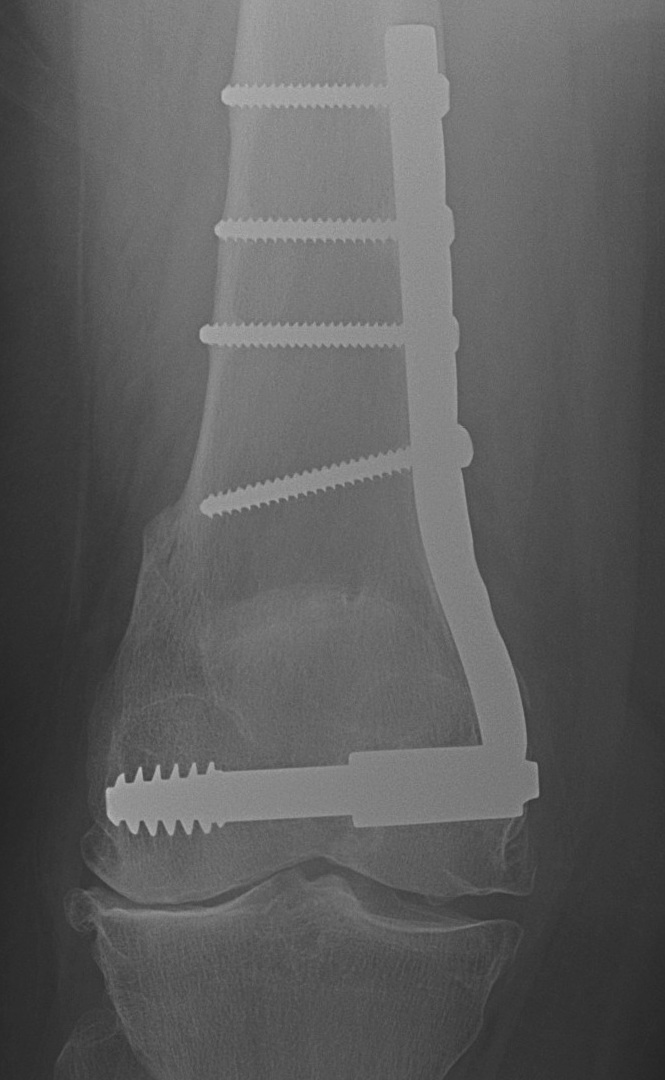

Lateral Opening Wedge Femoral Osteotomy

Advantage

- simple surgical approach

- single osteotomy cut

- more accurate correction

Disadvantages

- lengthen leg

- higher risk of non union

- better for smaller corrections

- plate often irritates iliotibial band

Distal femoral locking plate + bone graft